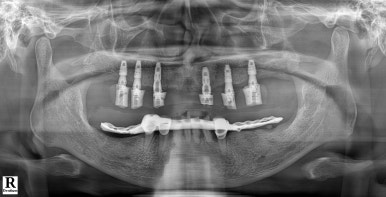

좌: 틀니를 착용하고 엑스레이를 찍은 모습, 우: 풀아치 임플란트를 식립한 직후 (2024년 7월 1일)